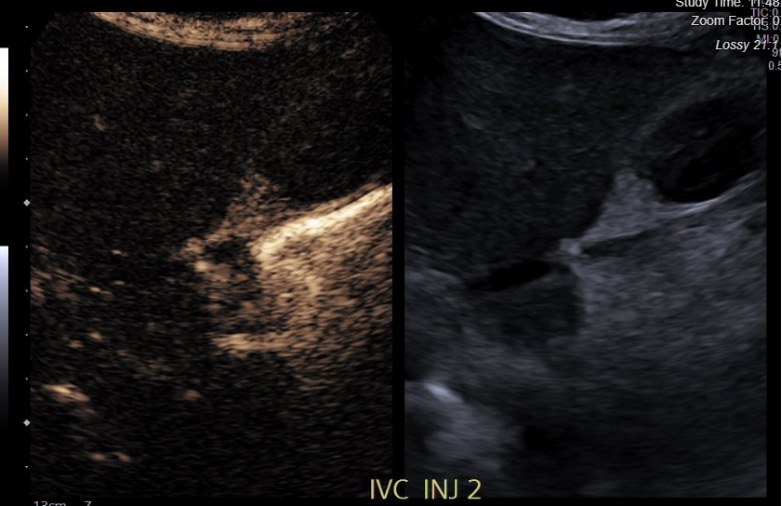

Introduction: Prompt radiographic evaluation is essential for early recognition of vascular complications following pediatric liver transplant (LT). Bedside contrast enhanced ultrasound (CE-US) is a non-invasive modality that avoids radiation exposure, the need for sedation and transport, and has potential to detect early post-LT vascular complications.We describe our initial experiences with its use as a screening and for-cause (FC) modality.

Methods: Retrospective analysis was performed on 20 CE-US in 14 pediatric patients undergoing partial (n=5) or whole graft (n=9) LT, between October 2024 and January 2026 at our institution. Intravenous LUMASON® (sulfur hexafluoride lipid-type A microspheres) was administered per protocol. Demographic, clinical, and radiographic data were analyzed. CE-US findings were correlated with standard of care imaging.

Results: Mean patient age was 7 years old and 57% were females. Indications for transplant included 5 Primary Cholestatic Conditions, 1 Glycogen Storage Disorder, 1 Giant Cell Hepatitis, 2 Autoimmune Hepatitis, 2 Unresectable Hepatic tumors, 2 Acute on Chronic Liver Failure, and 1 Cystic Fibrosis. Compared to standard of care imaging, 6 FC CE-US accurately identified 7 of 8 abnormalities (decreased arterial flow (n=1), asymptomatic arterial anomaly (n=1), IVC stenosis/thrombosis (n=4), parenchymal hypoperfusion (n=1) with 87% sensitivity and 100% specificity. 1 arterial stenosis diagnosed on CTA was not identified on FC CE-US. 4 findings on FC CE-US helped change management. 3 of 14 screening CE-US demonstrated one previously known asymptomatic arterial anomaly and 2 cases of initial poor parenchymal perfusion. The timing of post-operative CE-US varied (mean day post-LT 2.2). There was no standardized reporting of CE-US findings. Contrast enhancement added $90 per study.

Conclusions: Bedside CE-US was safe and affordable with high sensitivity and specificity in pediatric LT recipients. It provided effective and timely diagnosis avoiding the need for anesthesia and transport. Further efforts necessitate prospective study with correlation to standard of care imaging and clinical outcomes, as well as need for the standardized reporting of CE-US findings.